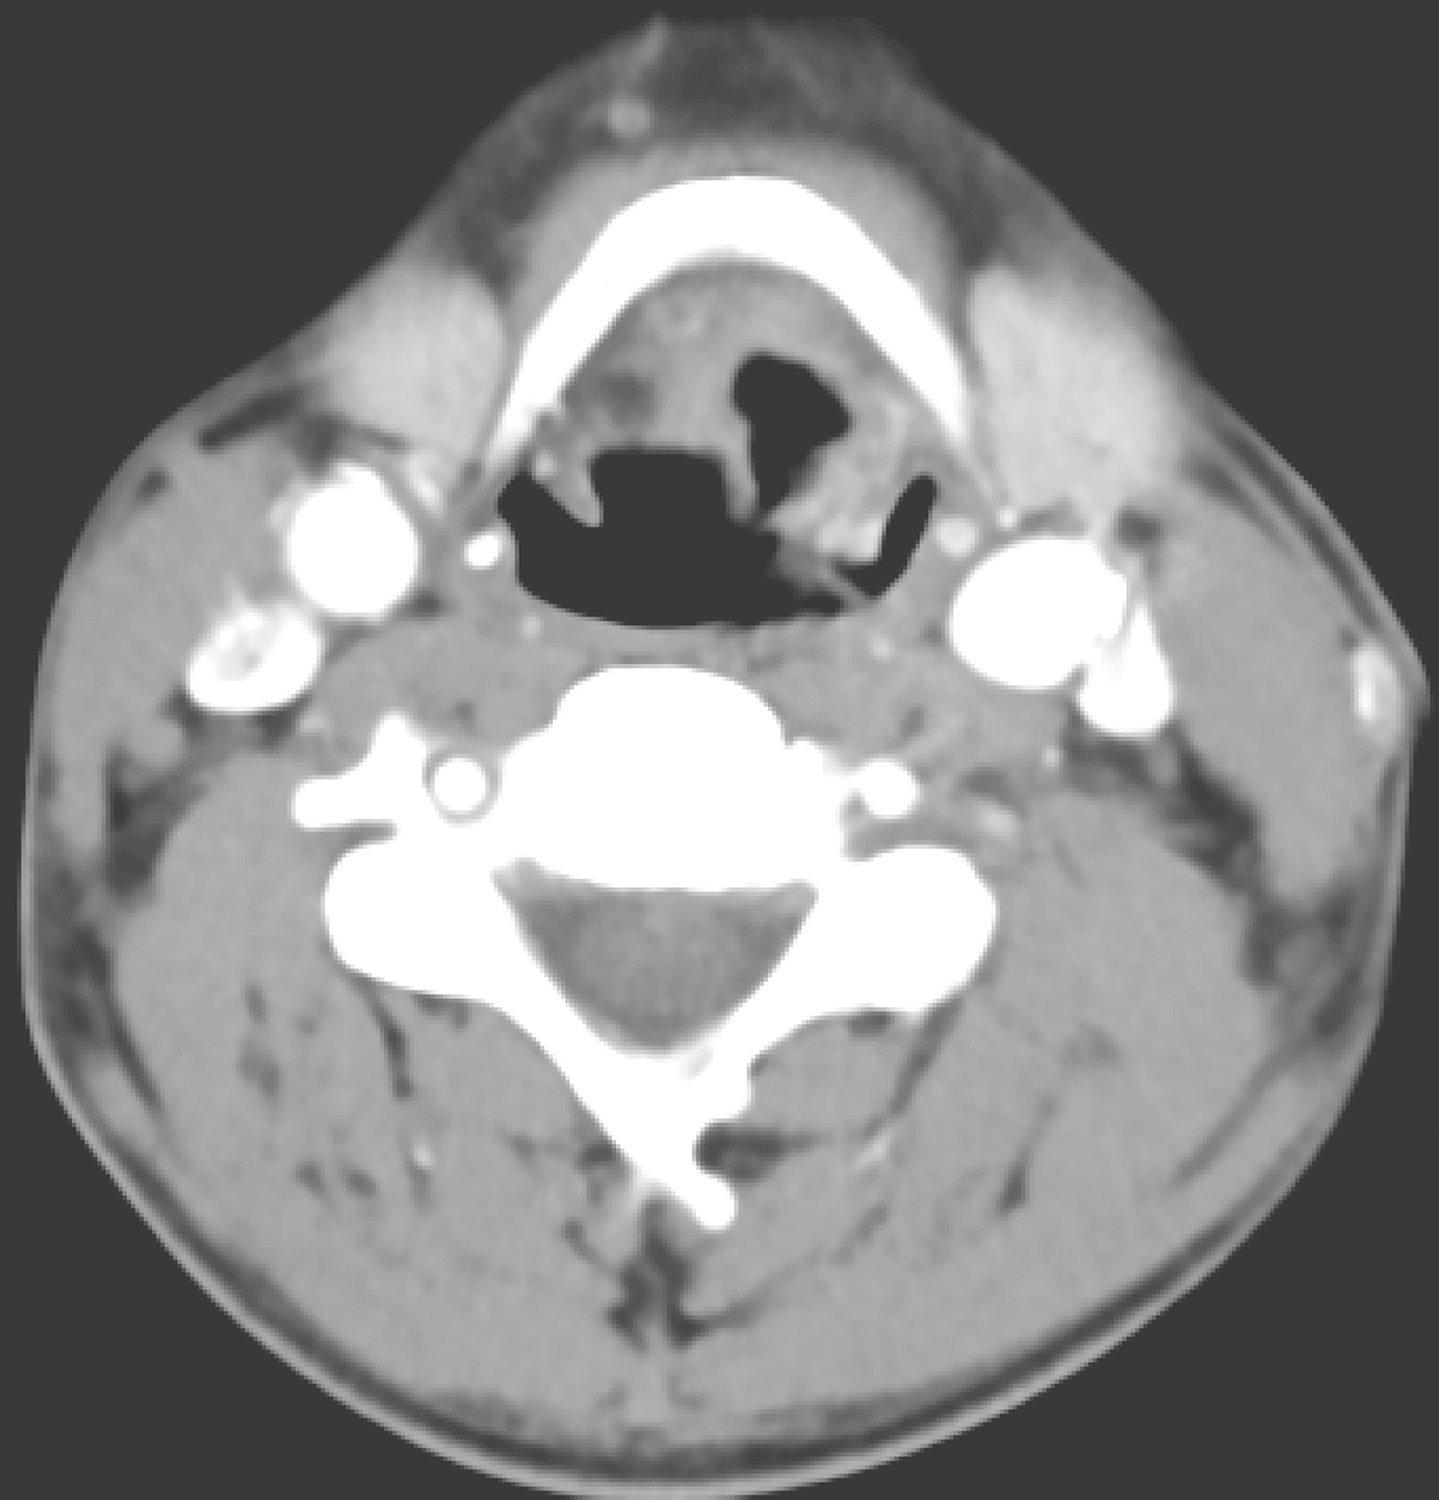

1.2014年10月30日颈胸部CT

检查所见:会厌舌面软组织影不规则增厚,呈较明显强化,以左侧份为著,表面不规则,似见较深溃疡,病变向前累及左侧舌会厌谷、会厌前间隙,可疑累及左侧舌根部,左侧舌根部软组织影增厚(图1)。相邻左侧勺状会厌皱襞略增厚。

图1 会厌舌面新生物,可疑累及左侧舌根

左侧颈深上组可见肿大淋巴结,约1.4cm×1.6cm(图2)。

图2 左颈Ⅱ区肿大淋巴结

余双颈部、双侧肺门、纵隔未见明确肿大淋巴结。

鼻窦、口咽、梨状窝、双侧喉室及甲状腺未见异常。

影像学诊断:

(1)喉癌,声门上型,侵犯范围如上所述。

(2)左上颈部淋巴结转移。

(3)双侧肺气肿。双上肺陈旧病变可能性大。